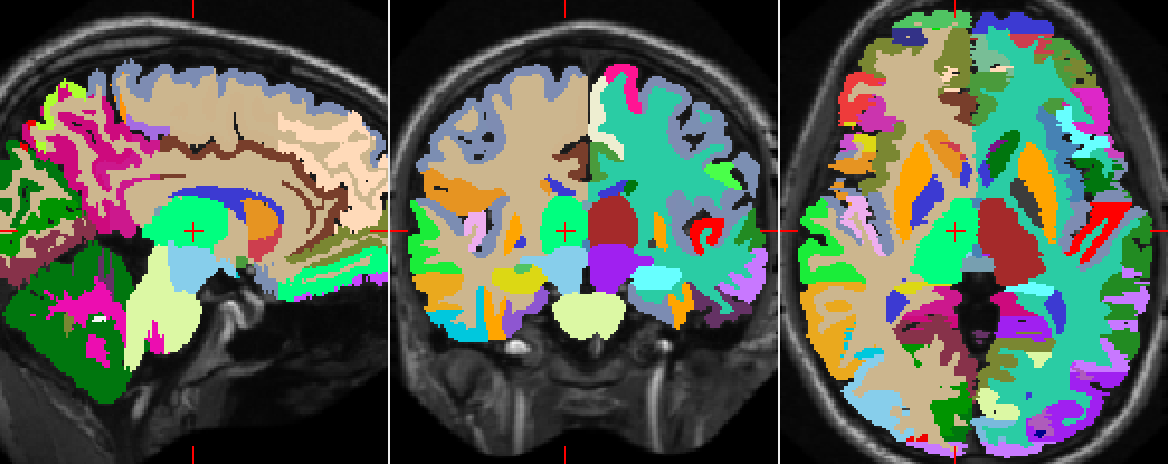

Refer to caption

(a)

(b)

(c)

Figure 6: Comparison of the automatic and manual segmentations of the cerebral white matter region (in green) of the right hemisphere of an example MRI (ID: 1004). (6(a)) Segmentation returned by the network using only the three orthogonal 2D patches as inputs, (6(b)) Manual segmentation, (6(c)) Segmentation returned by SegNet. Contrary to (6(c)), (6(a)) wrongly classifies some parts of the left hemisphere.

Figure 6 illustrates how well the downscaled patches and the distances to centroids enforce the global spatial consistency of the segmentations. Figure 7 shows the manual and automatic segmentations of a particular MRI. We notice that the misclassified voxels tend to lie on the boundaries of the regions, as expected.